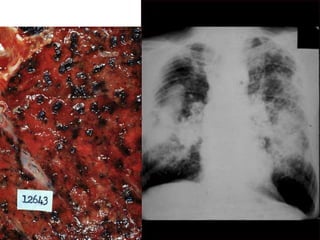

Patron micronodular TBC miliar

Hepatizacion pulmonar (consolidacion)